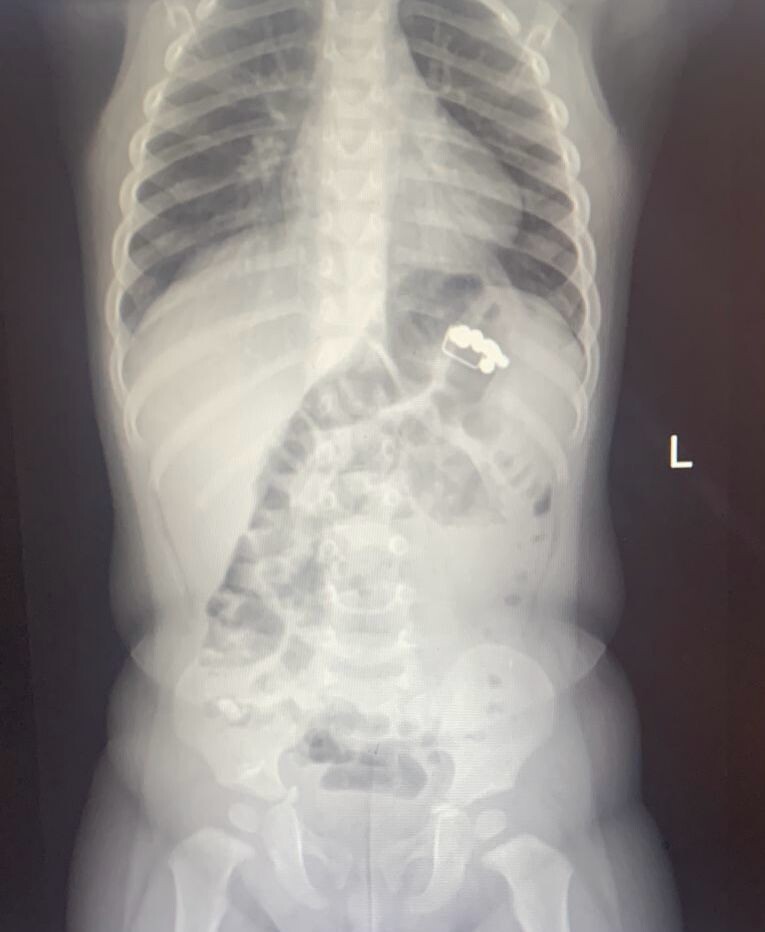

Медики подозревали, что у крохи ОРВИ, однако после того, как его отправили на рентген, увидели ряд инородных предметов в области ЖКТ ребёнка. Об этом рассказали в пресс-службе воронежского Минздрава.

Детские хирурги подтвердили диагноз и госпитализировали ребенка для наблюдения и лечения.

Под общим наркозом эндоскопист Александр Климов экстренно удалил магниты и скрепку. В процессе операции он выявил два «точечных» пролежня желудка.

«А контрольный рентгеновский снимок показал еще два магнита, которые после постановки очистительной клизмы вышли естественным путём», – отметили врачи.